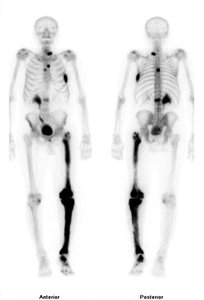

Some isotopes are radioactive and can emit energy and particles.

Radioactive isotopes are used in medicine, such as Tc-99 for diagnostic imaging.